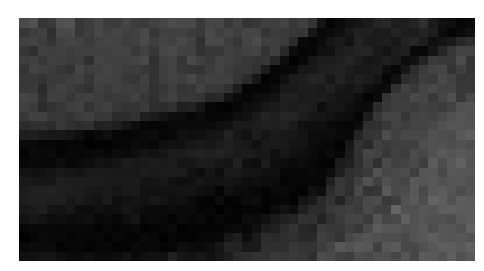

Figure 3: Reconstructions results. Rows 1 and 3: Examples of comparing the ground truth (GT) fully sampled image to the reconstructed images obtained by the three models (1-3), NPB-REC, baseline, E2E-VarNet trained with Dropout, and the NPB-REC std. map at accelerations R=4𝑅4R=4, R=8𝑅8R=8, respectively. Rows 2 and 4: The corresponding annotated ROIS of Nonspecific white matter lesions.

Fig. 3 presents examples of reconstruction results obtained by (1) our NPB-REC approach, (2) the baseline, and (3) Monte Carlo Dropout, for equispaced masks with two different acceleration rates R=4𝑅4R=4 and R=8𝑅8R=8. The reconstructed images predicted by the three models are smoother than the reference image. This is due to the fact that all the models were trained with SSIM loss, which tends to produce overly smooth reconstructions while preserving the diagnostic content and the anatomical features Sriram et al. (2020a). These images can be enhanced by dithering the image by adding a small amount of random Gaussian noise to produce a more textured reconstruction, as proposed in Sriram et al. (2020b).

Table 1 presents the mean PSNR and SSIM metrics, calculated over the whole inference set, for the three models. Our NPB-REC approach achieved significant improvements over the other methods in terms of PSNR and SSIM (Wilcoxon signed-rank test, pmuch-less-than\ll1e-4, except for SSIM values in line W, R=4𝑅4R=4 where they are roughly the same for NPB-REC and Baseline). The improvement in the reconstruction performance can be noted both quantitatively from the metrics, especially for masks with acceleration rate R=8𝑅8R=8, and qualitatively via the images of annotations, where our results show less smoothness than those obtained by Dropout.